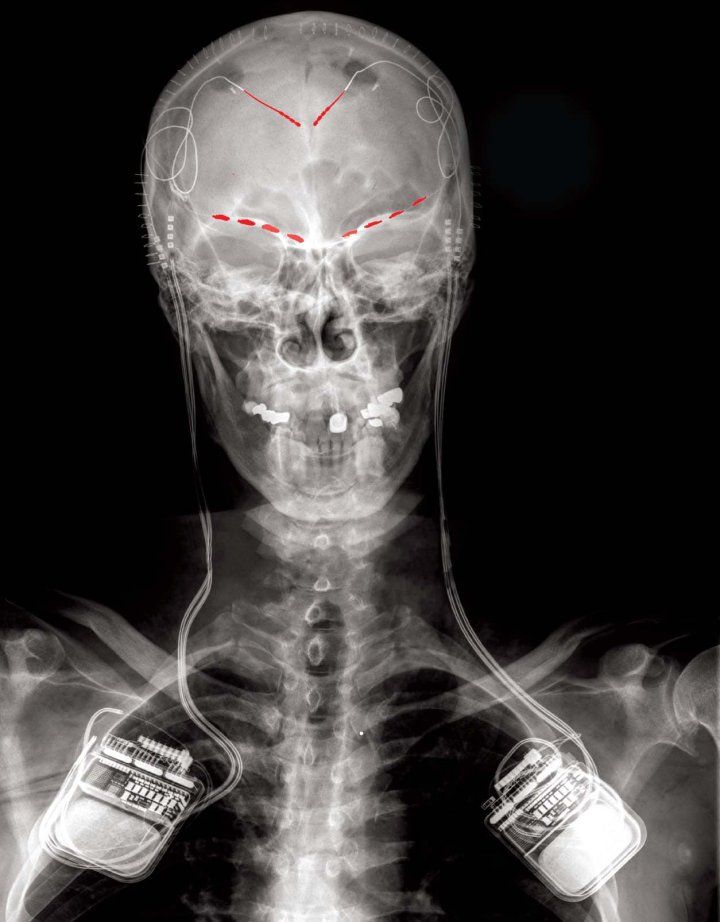

Frontal x-ray image of one study participant showing implanted brain recording electrodes (in red) connected to a bidirectional brain stimulating and recording implant on both sides of the body.

In a new study, reported May 22 in Nature Neuroscience, Shirvalkar and his colleagues looked for those biomarkers by implanting a neural recording device in the anterior cingulate cortex (ACC) and orbitofrontal cortex (OFC) of four people (three with post-stroke pain and one with phantom limb pain).

“The device we implanted into the participants in this study is actually a deep brain stimulation device that has the capability not only to sense and record brain activity, but also to provide electrical stimulation when needed,” says Philip Starr, M.D., Ph.D., professor of neurological surgery and a senior author of the study. “The hope is that by pinpointing the specific brain signals underlying someone’s pain experience, we can program the device to deliver stimulation only when those signals are detected and return the brain’s pain networks to a normal, healthy state.”